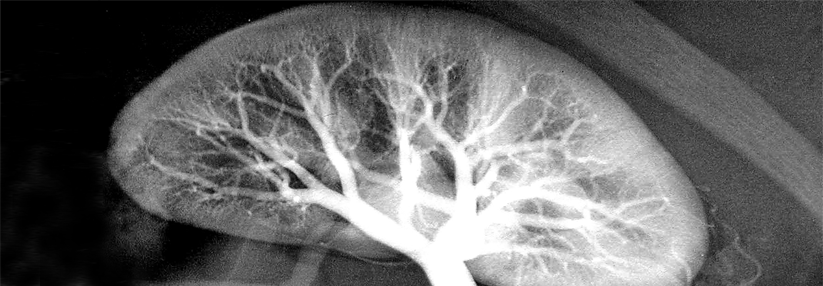

Nur selten besteht ein kausaler Zusammenhang zwischen jodhaltigem Kontrastmittel und einem akuten Organversagen. Nur selten besteht ein kausaler Zusammenhang zwischen jodhaltigem Kontrastmittel und einem akuten Organversagen. © Bergringfoto – stock.adobe.com

Jodhaltige Kontrastmittel (KM) erhöhen die Aussagekraft vieler CT-Scans deutlich. Dennoch erhielten Patienten mit eingeschränkter Nierenfunktion diese Untersuchungen bisher nicht oder nur mit Verzögerung, weil man ein Kontrastmittelinduziertes akutes Nierenversagen (ANV) fürchtete.

Historisch unterschied man allerdings in zugrunde liegenden Studien nicht zwischen KM-assoziierten und tatsächlich ursächlich bedingten akuten Nierenschäden. Darin dürfte der Grund liegen, dass die Gefahr für KM-abhängige ANV überschätzt wird, konstatieren Professor Dr. Matthew S. Davenport von den Departments of Radiology und Urology der Michigan Medicine am Medical Center in Ann Arbor und Kollegen.

KM-induziertes akutes Nierenversagen tritt per Definition innerhalb von 48 Stunden nach Verabreichung des Kontrastmittels auf, wobei andere nephrotoxische Faktoren ausgeschlossen sein sollten. Das aber gelingt in der Praxis nur selten. Der Terminus KM-assoziiertes ANV bezeichnet dagegen jedes akute Nierenversagen, das innerhalb von 48 Stunden nach Kontrastmittelgabe auftritt. Es kommt deutlich häufiger vor, wobei seine Rate abhängig von der geschätzten glomerulären Filtrationsrate (eGFR) ist.